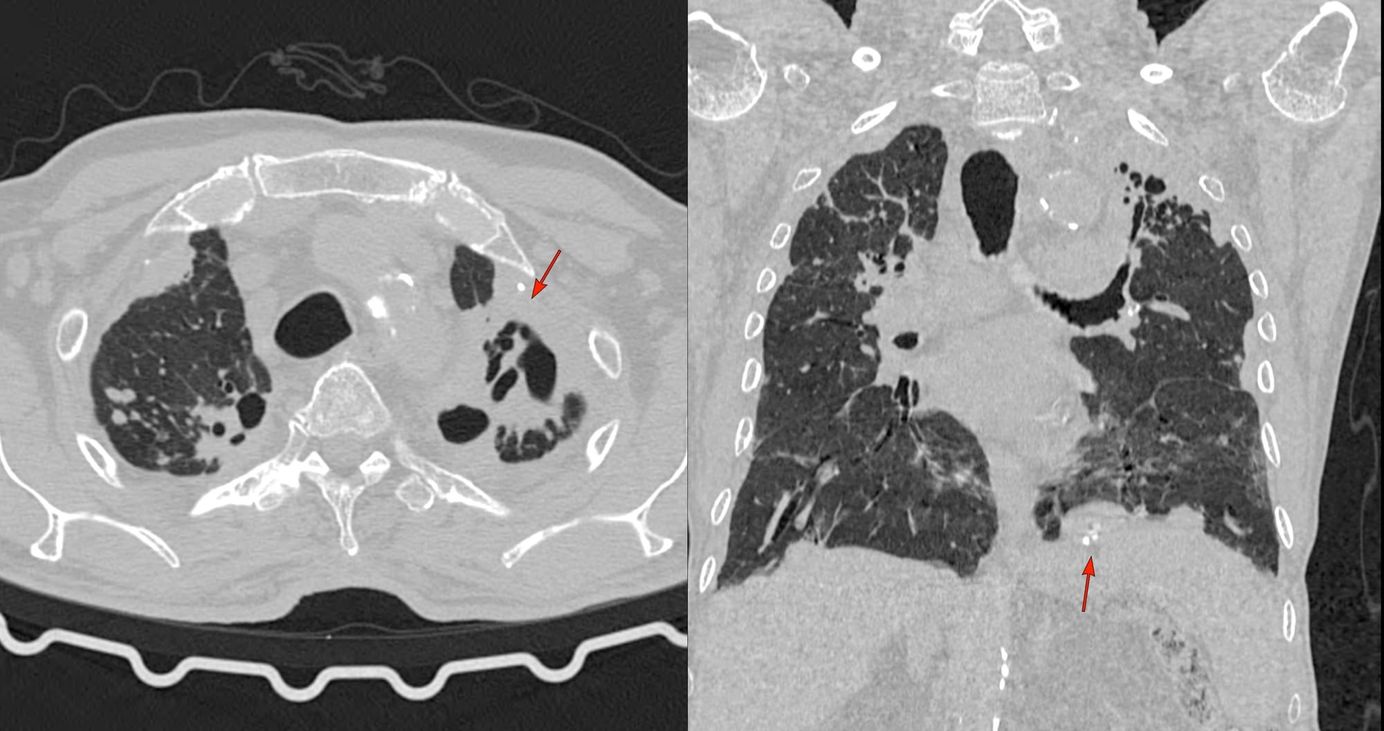

The PDIF sign is basically the presence of a fibrosing ILD typically compacted within the last 2 cm of the peridiaphragmatic lung and may suggest not just CTD-ILD but specifically myositis ILD